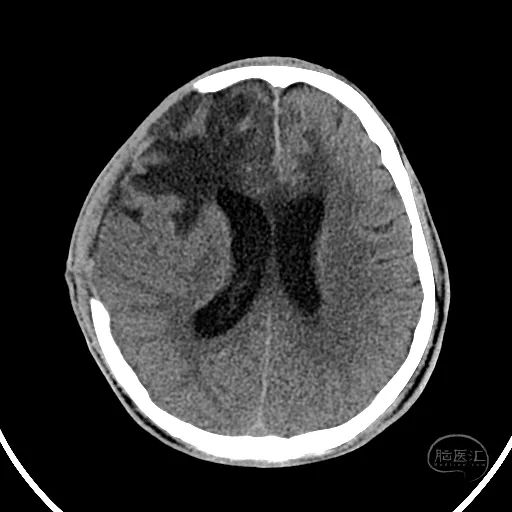

颅脑CT可见左侧小脑半球挫裂伤,第四脑室明显受压。

右额叶脑挫裂伤并血肿,侧脑室额角受压,脑室无明显扩张。

中线结构稍向左侧偏移。

2小时后复查颅脑CT显示第四脑室受压消失。

小脑挫伤灶水肿较前加重,脑干及小脑半球低密度改变。

硬膜外血肿无明显变化。

右额叶脑挫裂伤并脑内血肿形成,中线结构明显移位。

左侧脑室有扩张表现。